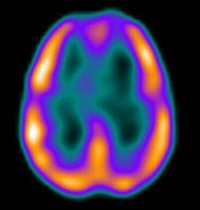

A stroke az agy tartós vérellátási zavara. Két főbb típusa; az isémiás, azaz elzáródásos, és a hemorrágiás, másnéven vérzéses stroke. Előbbi esetben egy elszabadult vérrög az agyba jutva részlegesen (TIA), súlyosabb esetben pedig az ér teljes keresztmetszetében (stroke) elzárja az áramló vér útját.